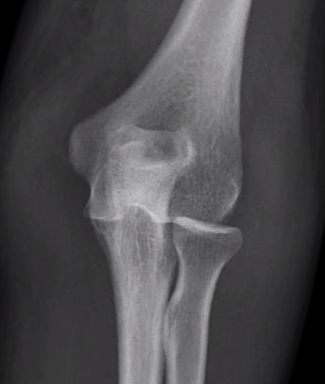

3. Confirm concentric reduction on xray

Not concentrically reduced on xrays